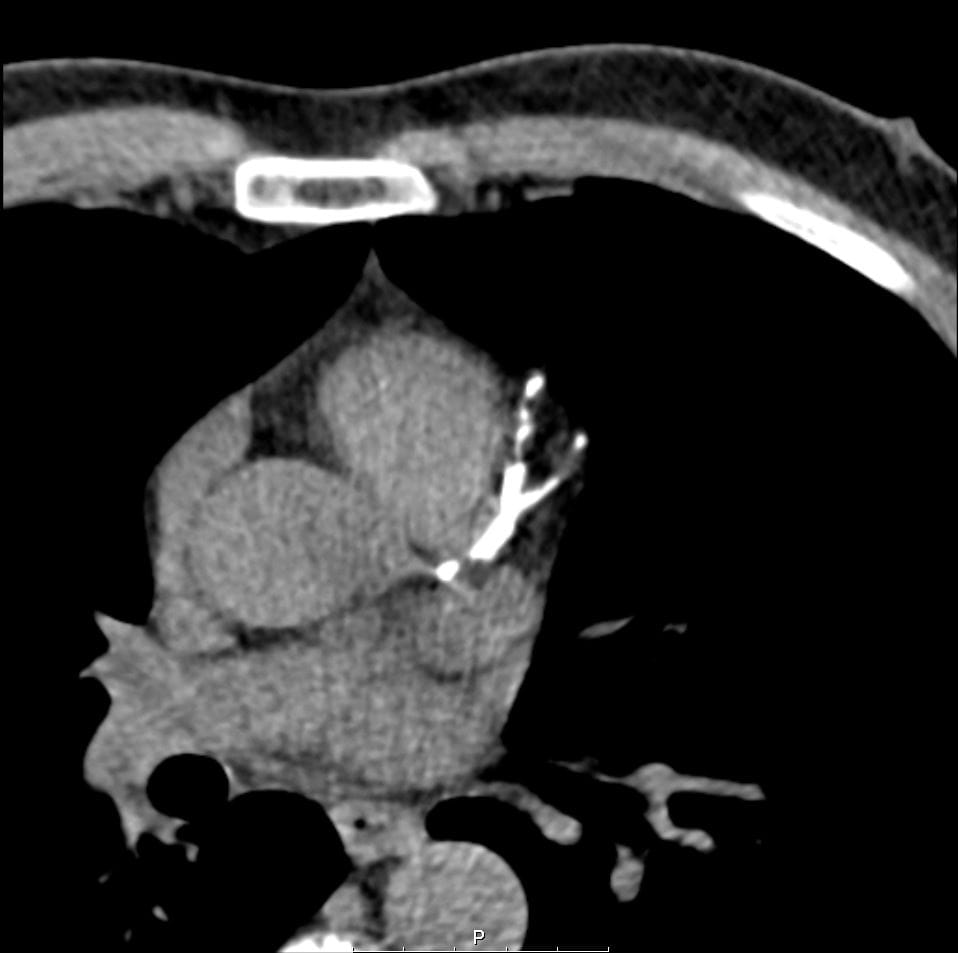

One patient story highlights the potential of CLARIFY to prevent an impending cardiac event. A 56-year-old man had high blood pressure, high cholesterol and a family history of heart disease. He had the opportunity to receive no-charge CAC, which flagged an extremely elevated risk level of 1274.

“Calcium deposits were distributed over all three coronary vessels, including the left main coronary artery,” says Sadeer Al-Kindi, MD, a cardiologist at UH Harrington Heart & Vascular Institute specializing in advanced cardiovascular imaging and an Assistant Professor at the School of Medicine.

The patient underwent a stress test that showed equivocal results and was deemed indeterminate. An elective heart catheterization showed complete occlusion of the left anterior descending artery, left circumflex artery and the end-segment of the right coronary artery.

“Given his extensive blockages, University Hospitals heart surgeons performed coronary artery bypass surgery,” Dr. Al-Kindi says. “The CAC screening alerted us to a risk that might have not been addressed based on symptom presentation, and the patient experienced excellent outcomes.”